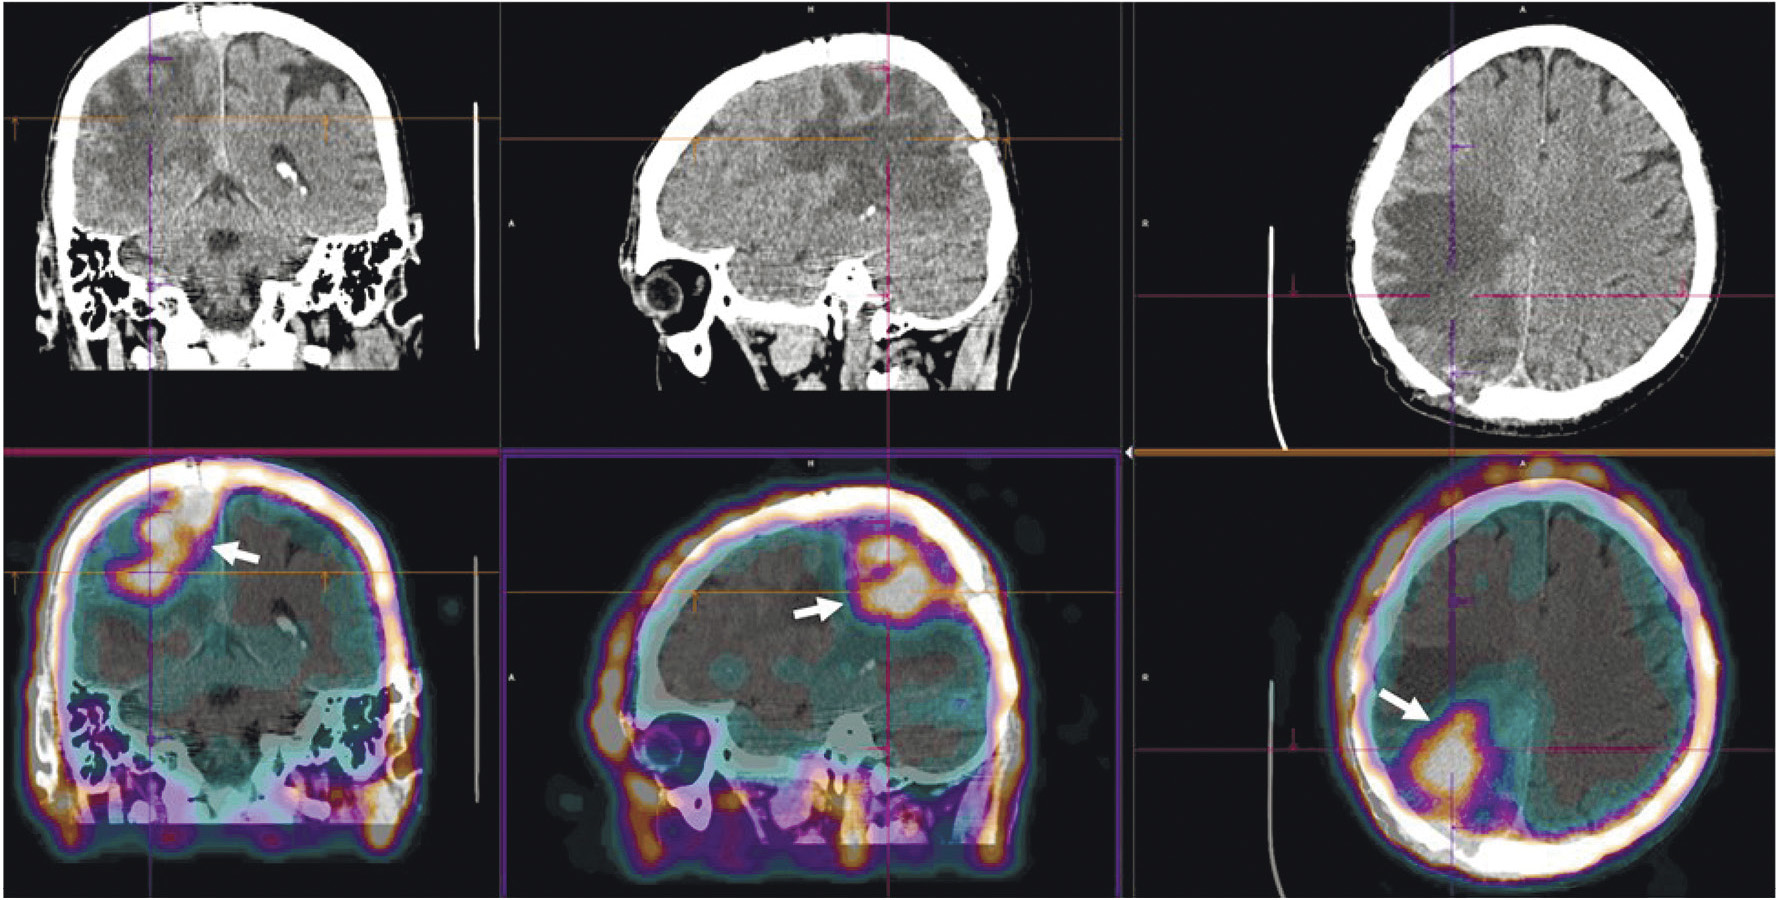

В НИИ онкологии Томского НИМЦ завершены первые фазы клинических исследований нескольких меченных технецием-99м каркасных белков (DARPin, ADAPT, Affibody), обладающих высокой аффинностью к рецептору эпидермального фактора роста второго типа (HER2/neu). Все препараты показали хорошую эффективность определения гиперэкспрессии рецептора HER2/neu при раке молочной железы и стадировании заболевания (рис. 1) [10, 11]. Кроме того, установлена возможность проведения ОФЭКТ/КТ с препаратами на базе скаффолдов для оценки эффекта терапии (рис. 2). Помимо основы РФЛП для диагностики злокачественных новообразований, каркасные белки могут служить вектором доставки при создании таргетных соединений для лечения злокачественных новообразований с гиперэкспрессией рецептора HER2/neu [13].

Рис. 2. ОФЭКТ/КТ-изображение пациентки с HER2/neu-позитивным раком правой молочной железы до начала лечения, выполненное через 2 ч после введения 99mTc-DARPIN-G3 (а), стрелками обозначены первичная опухоль (SUVmax = 3.1), метастазы в лимфатические узлы (SUVmax = 8.8) и кости; ОФЭКТ/КТ-изображение той же пациентки после двух курсов терапии транстузумабом через 2 ч после введения 99mTc-DARPIN-G3 (б), стрелками обозначена первичная опухоль (SUVmax = 0.55), метастазы не визуализируются

Радиофармпрепарат 99mTc-1-Тио-D-глюкоза и набор для его приготовления разработаны в НИИ онкологии Томского НИМЦ и ТПУ (“Тиоскан, 99mТс”, Россия). Неповреждённый гематоэнцефалический барьер непроницаем для данного препарата, поэтому 99mTc-1-Тио-D-глюкоза хорошо показала себя в диагностике опухолей головного мозга (рис. 7) [43]. Кроме того, ОФЭКТ/КТ с 99mTc-1-Тио-D-глюкозой рекомендована для стадирования и прогноза результатов лечения лимфопролиферативных заболеваний (рис. 8) [44, 45].

Рис. 7. ОФЭКТ/КТ с 99mTc-1-Тио-D-глюкозой пациента с рецидивом глиобластомы. Стрелками обозначено накопление РФЛП в опухоли